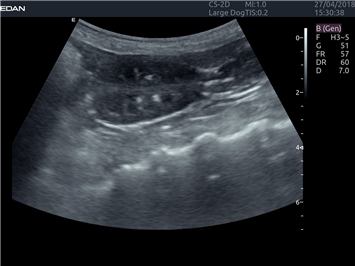

УЗИ-аппарат

EDAN Acclarix LX4 VET

Расширьте свои представления. Когда речь заходит о стабильности, производительности и эффективности, существует одна ультразвуковая система, которая расширяет возможности ветеринарных исследований.

EDAN Acclarix LX4 VET представляет собой профессиональную ультразвуковую систему, специально разработанную для ветеринарных исследований. Сочетание стабильности, высокой производительности и эффективности делает эту систему идеальным выбором для современной ветеринарной практики.